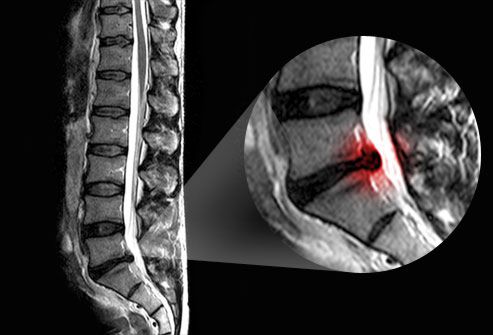

A causa mais comum de ciática é um disco de hérnia. Os discos agem como almofadas entre as vértebras da coluna vertebral. Esses discos ficam mais fracos com a idade e se tornam mais vulneráveis a lesões. Às vezes, o centro em forma de gel de um disco empurra seu revestimento externo e pressiona as raízes do nervo ciático. Cerca de 1 em cada 50 pessoas terá um hérnia de disco em algum momento da vida. Até um quarto deles terá sintomas que duram mais de 6 semanas.

O seu médico pode solicitar exames de imagem, como uma ressonância magnética, para obter mais informações sobre a localização e a causa do nervo irritado. Uma ressonância magnética pode mostrar o alinhamento dos discos, ligamentos e músculos vertebrais. Uma tomografia computadorizada com contraste também pode fornecer uma imagem útil da medula espinhal e dos nervos. Determinar a causa da ciática pode ajudar a orientar o curso do tratamento. Os raios X podem ajudar a identificar anormalidades ósseas, mas não conseguem detectar problemas nos nervos.